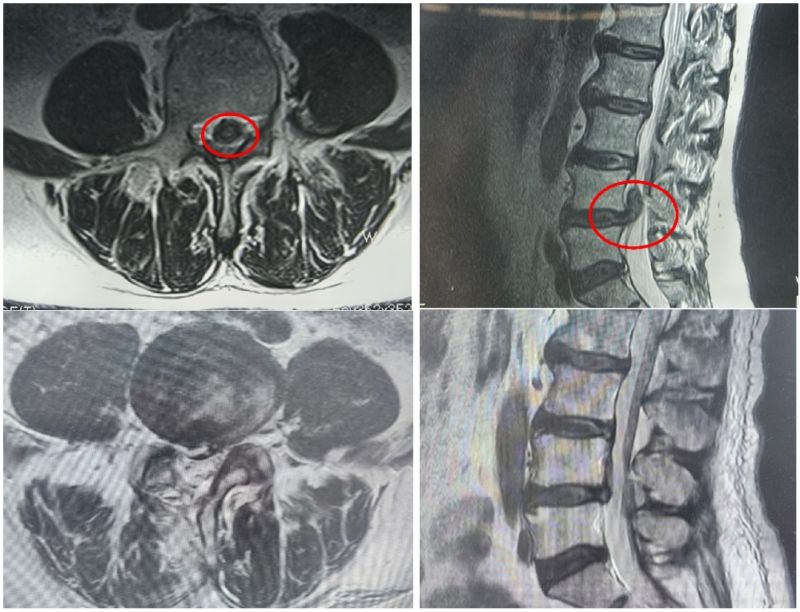

骨科三病區李鵬主任詳細詢問病情并查體,結合腰椎磁共振,診斷為腰椎間盤突出癥伴神經根病。詢問病史,患者近1年來飽受疼痛折磨,夜不能寐,到多地醫院求醫,對開放手術心生恐懼,一直保守治療。了解病情后,李鵬主任團隊制定了UBE微創手術治療方案,為患者順利進行了單側雙通道入路內鏡下腰4-5椎間盤摘除術、脊髓神經根粘連松解手術。

術前、術后磁共振檢查

患者術中出血量不到20毫升,僅留下0.8厘米瘢痕。術后次日楊先生便可下地自由活動,腰腿疼痛感消失,走路也不再一瘸一拐,效果明顯,術后5天順利出院。患者及家人對李鵬主任帶領的醫護團隊表示衷心的感謝。